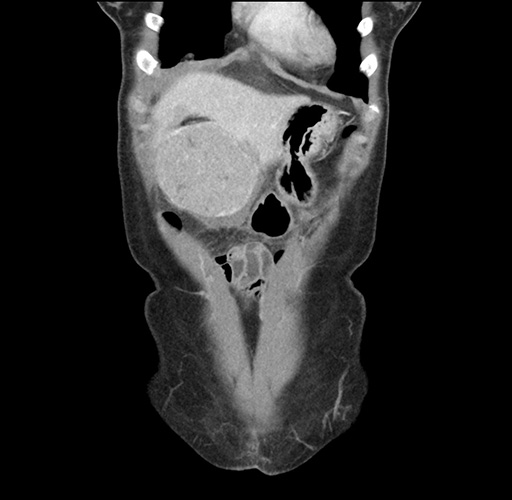

Imaging Analysis

Look through the patient's CT scan to identify any areas of concern for the necessary procedure.

Based on your CT findings, which issue(s) would give reason for "planned slowing down moment(s)" in this case?